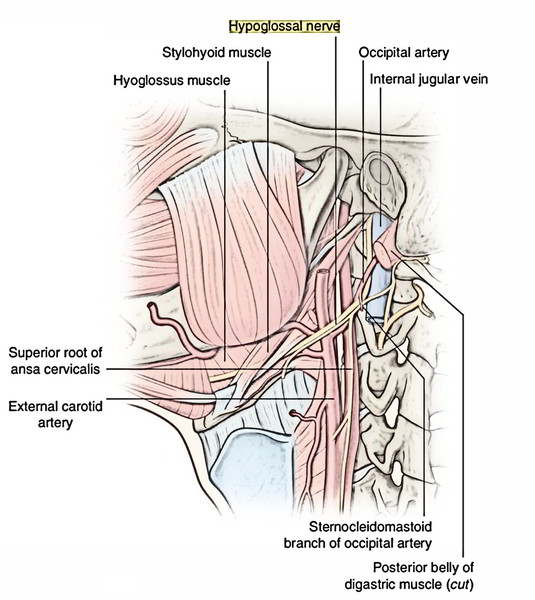

The Hypoglossal Nerve (CN XII) – Course – Motor – TeachMeAnatomy

Image result for ansa cervicalis | Hypoglossal nerve, Medical, Superior …

Hypoglossal Nerve (XII) and Canal

ICA and its relation to cranial nerves IXth, Xth, XIIth and sympathetic …

Hypoglossal nerve leaving the hypoglossal canal, right view. hn …

Hypoglossal nerve leaving the hypoglossal canal, right view. hn …